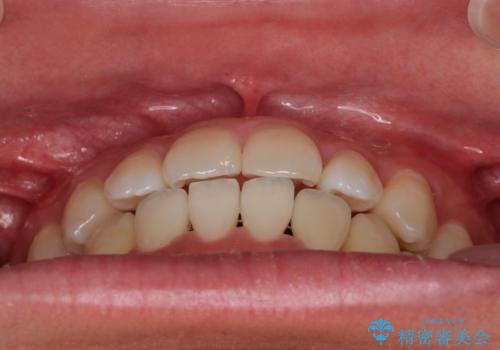

歯列弓の拡大により約1年で矯正治療を終えることができました。

正中も合わせることができ、非常にきれいに仕上がりました。